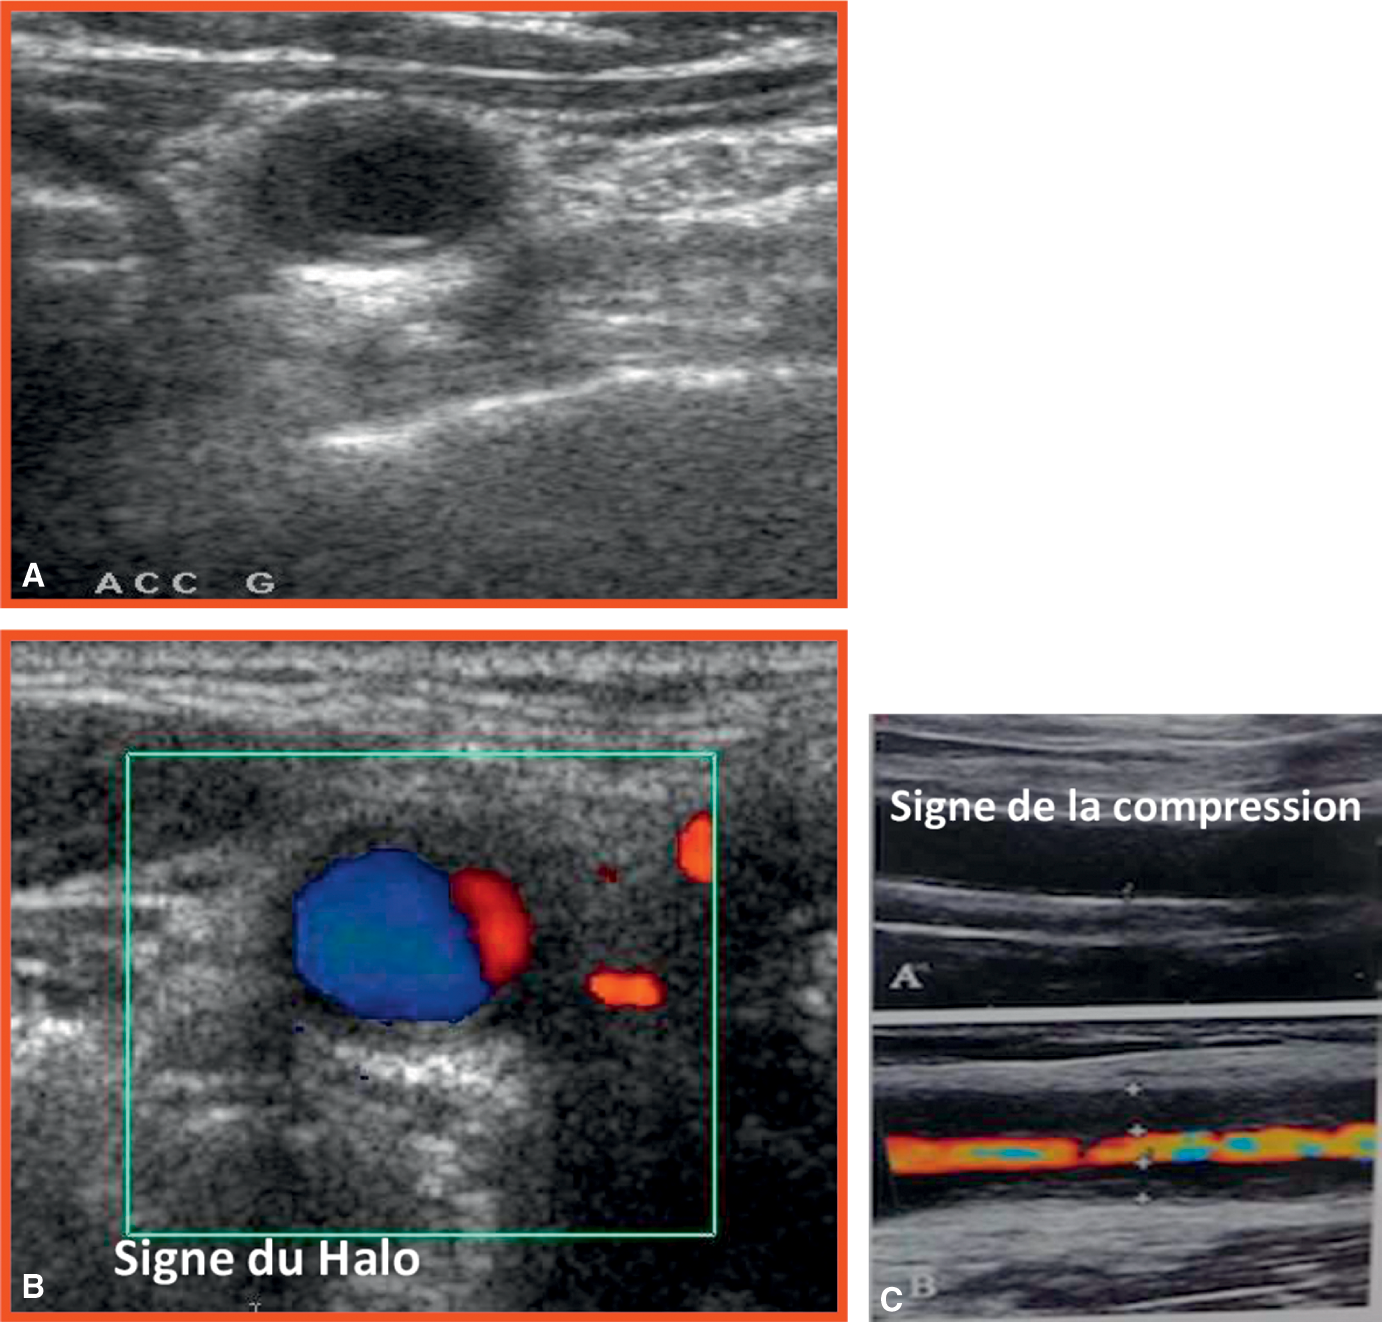

Fig. 16.6.

Échographie mode B et doppler des artères temporales.

A. Signe du halo en mode B. B. Signe du halo en mode doppler. C. Signe de la compression : en compression, la paroi de l’artère (hypoéchogène) reste visible, sans le flux doppler.

C’est l’examen de première intention en cas de suspicion d’ACG. L’échographie des axes vasculaires, notamment des artères temporales, peut révéler des signes caractéris- tiques d’artérite. Il est recommandé d’étudier également les gros vaisseaux du cou et les troncs supra-aortiques (artères carotides et axillaires).

Le signe pathognomonique est le signe du halo (halo hypoéchogène circonférentiel de la paroi du vaisseau). Une incompressibilité de l’artère, une occlusion ou une sté- nose peuvent aussi être observées. L’échographie (fig. 16.6) doit impérativement être réalisée par un opérateur entraîné sachant faire la différence entre un signe du halo et des lésions athéromateuses, fréquentes à cet âge. Cet examen peut donc per- mettre de confirmer le diagnostic ou de diriger la biopsie de l’artère afin d’améliorer la sensibilité diagnostique de cet examen.

La présence d’un signe du halo bilatéral a une spécificité de 100 % et permet devant un tableau clinico-biologique compatible de retenir le diagnostic d’ACG sans réaliser de biopsie d’artère temporale.

Signe du halo

Il consiste en un halo hypoéchogène circonférentiel au niveau de la paroi du vaisseau qui correspond à son inflammation, une hypoéchogénicité de l’intima du vaisseau touché par l’inflammation et, de manière moins spécifique, une sténose pouvant aller jusqu’à l’occlusion complète.